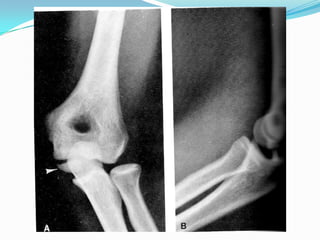

Avulsión del Epicóndilo

Avulsión de la Epitróclea

Luxación posterior con arrancamiento óseo a nivel del epicóndilo y la

epitróclea